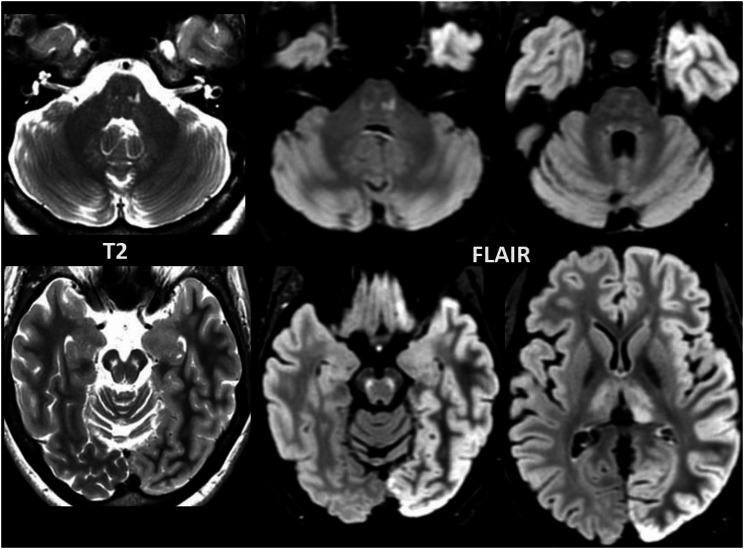

No abnormal contrast enhancement and no diffusion restriction were observed. In four patients atrophy of the brain stem disproportionate for age was noted, particularly of the midbrain and superior cerebellar peduncles. In patient 8, who presented with a stroke-like episode, the MRI showed cortical FLAIR hyperintensity and subtle cortical swelling of the left cerebral hemisphere, and presumably reactive hyperintensity of the left pulvinar (Fig. 4), in addition to AMACR-related abnormalities in the brain stem and thalami. In three patients, multifocal T2 hyperintensities of presumed vascular origin were observed in the cerebral white matter (patient 2, 6 and 7 at age 66, 62 and 52 years, respectively). In another patient confluent presumably vascular T2 hyperintensities were found in the cerebral white matter together with lacunar infarcts, small vermis infarcts and a cortical infarct (patient 4 at age 66).